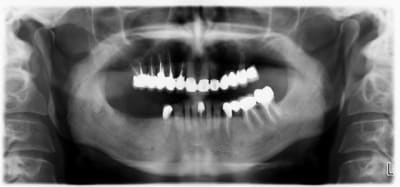

La pano est dégueulasse, à l'époque je n'avais pas encore la mienne, merci les radiologues.

-pas de lésions apicales visibles, les dents non dévitalisées répondent au test de vitalité.

-Pas de poches supérieures à 6 mm.

-La 23 est foutue, cariée jusqu'au trognon.

Pour compléter également, pas de mobilités, hormis 24/25. Pas de lésions furcatoires.

La 16 a été amputée de sa racine MV, mais le patient ne se souvient plus quand.

Patient relativement jeune (entre 50 et 60 ans)